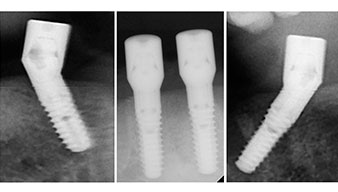

Le protocole chirurgical préconisé pour les implants utilisés (SKY, Bredent Medical) précise une vitesse de rotation de 1.200 tr./min. pour le pré-forage (Fig. 7 - 9).

Ceci correspond à la position suivante prédéfinie dans l'Implantmed. Nous voyons ici le contre-angle W&H tenu à un angle de 45° par rapport à la crête dans la région de 45 afin de préserver le nerf mentonnier. Le trou mentonnier sert de repére anatomique à tous les forages de cette région. Les forages suivants ont été effectués à la vitesse réduite de 300 tr./min. (Fig. 10 et 11).